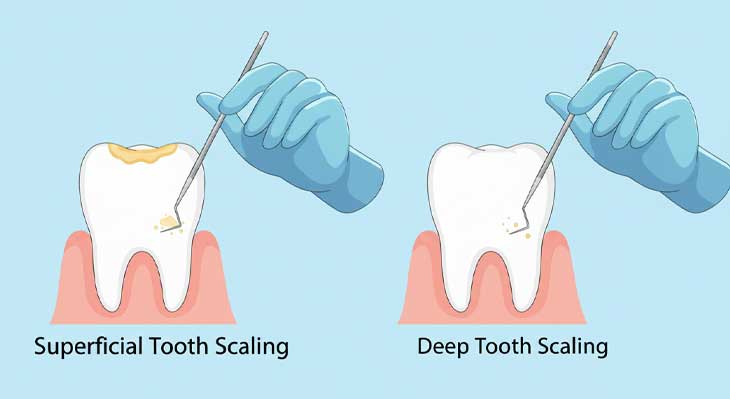

جرم گیری دندان بر اساس عمق و میزان تجمع جرم و وضعیت سلامت لثه، به دو دسته اصلی تقسیم می شود. انتخاب نوع مناسب درمان، پس از معاینه دقیق توسط دندانپزشک و با استفاده از ابزاری به نام پروب پریودنتال که عمق شیار لثه را اندازه گیری می کند، صورت می گیرد. درک تفاوت این دو روش برای آگاهی از وضعیت سلامت دهان و دندان بسیار مهم است.

جرم گیری سطحی (پروفیلاکسی): این همان جرم گیری روتین و پیشگیرانه است که برای حذف پلاک و جرم های تجمع یافته در بالای خط لثه (نواحی قابل مشاهده) انجام می شود. این روش برای افرادی که لثه های سالم دارند و صرفا برای حفظ بهداشت و جلوگیری از بروز بیماری مراجعه می کنند، مناسب است. این درمان معمولا بدون درد است، نیازی به بی حسی ندارد و در یک جلسه کوتاه انجام شده و با بروساژ و پولیش سطح دندان ها به پایان می رسد تا از تجمع مجدد پلاک جلوگیری شود.

جرم گیری عمقی (روت پلنینگ): این یک روش درمانی برای بیماری لثه (پریودنتیت) است. در این روش، جرم ها و باکتری های نفوذ کرده به زیر خط لثه و داخل پاکت های پریودنتال (فاصله ایجاد شده بین لثه و دندان) پاکسازی می شوند. این فرآیند حتما با بی حسی موضعی انجام می شود و علاوه بر حذف جرم، سطح ریشه دندان نیز صاف و صیقلی می گردد تا بستر مناسبی برای اتصال مجدد لثه به دندان فراهم شود. این درمان معمولا در چند جلسه انجام می شود.

به طور خلاصه، هدف از جرم گیری سطحی، پیشگیری است، در حالی که هدف از جرم گیری عمقی، درمان و متوقف کردن پیشرفت انواع بیماری لثه و جلوگیری از تحلیل استخوان و از دست دادن دندان است